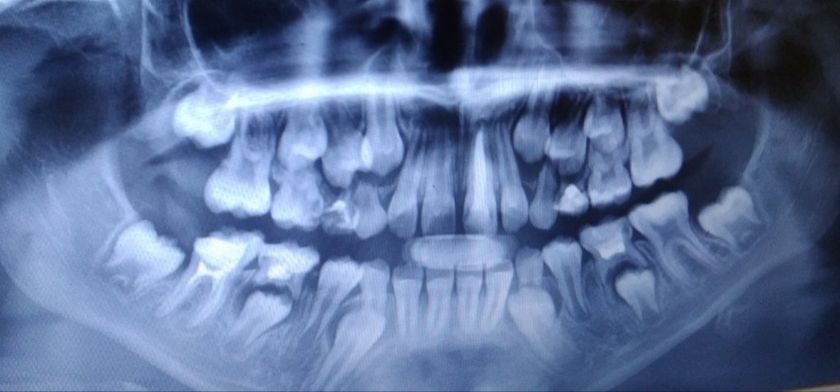

У старшей вчера заболел зуб(5ка вверху) рядом с удаленным на прошлой неделе молочным(4ка). Сегодня дочь с папой ездили в клинику. Им сказали надо удалять. Сам зуб уже леченный, но с удалением соседнего оголился нерв. Лечить его не берут (не знаю всех нюансов), записали на завтра удалять. Я расстроена до слез. Там ещё не лезет постоянный, переживаю чем она жевать будет(внизу и вверху удалено по зубу). С другой стороны внизу нет одного. Беда???искать другого врача или довериться и удалить? Бедная моя девочка. Фото до удаления зубов.

Как много зубов лезет сразу!!!!

Ага, и сами не выпадают, приходится драть☹️